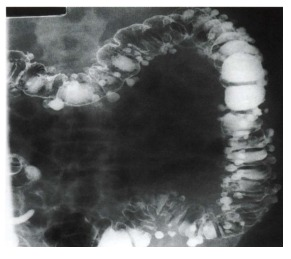

O enema opaco com duplo contraste ilustrado a seguir evidencia uma doença bastante prevalente. A respeito desta doença, assinale a alternativa CORRETA: